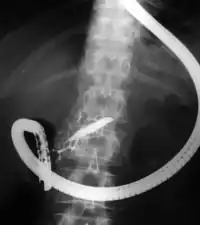

Endoscopic retrograde cholangiopancreatography (ERCP) is a technique that combines the use of endoscopy and fluoroscopy to diagnose and treat certain problems of the biliary or pancreatic ductal systems. It is primarily performed by highly skilled and specialty trained gastroenterologists. Through the endoscope, the physician can see the inside of the stomach and duodenum, and inject a contrast medium into the ducts in the biliary tree and pancreas so they can be seen on radiographs.

The patient is sedated or anaesthetized. Then a flexible camera (endoscope) is inserted through the mouth, down the esophagus, into the stomach, through the pylorus into the duodenum where the ampulla of Vater (the union of the common bile duct and pancreatic duct) exists. The sphincter of Oddi is a muscular valve that controls the opening to the ampulla. The region can be directly visualized with the endoscopic camera while various procedures are performed. A plastic catheter or cannula is inserted through the ampulla, and radiocontrast is injected into the bile ducts and/or pancreatic duct. Fluoroscopy is used to look for blockages, or other lesions such as stones.[8][9]

When needed, the sphincters of the ampulla and bile ducts can be enlarged by a cut (sphincterotomy) with an electrified wire called a sphincterotome for access into either so that gallstones may be removed or other therapy performed.[10]

Other procedures associated with ERCP include the trawling of the common bile duct with a basket or balloon to remove gallstones and the insertion of a plastic stent to assist the drainage of bile.[11] Also, the pancreatic duct can be cannulated and stents be inserted.